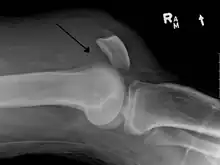

Quadriceps tendon rupture in plain X-ray

Quadriceps tendon rupture in plain X-ray: Incomplete rupture with haematoma in tendon.